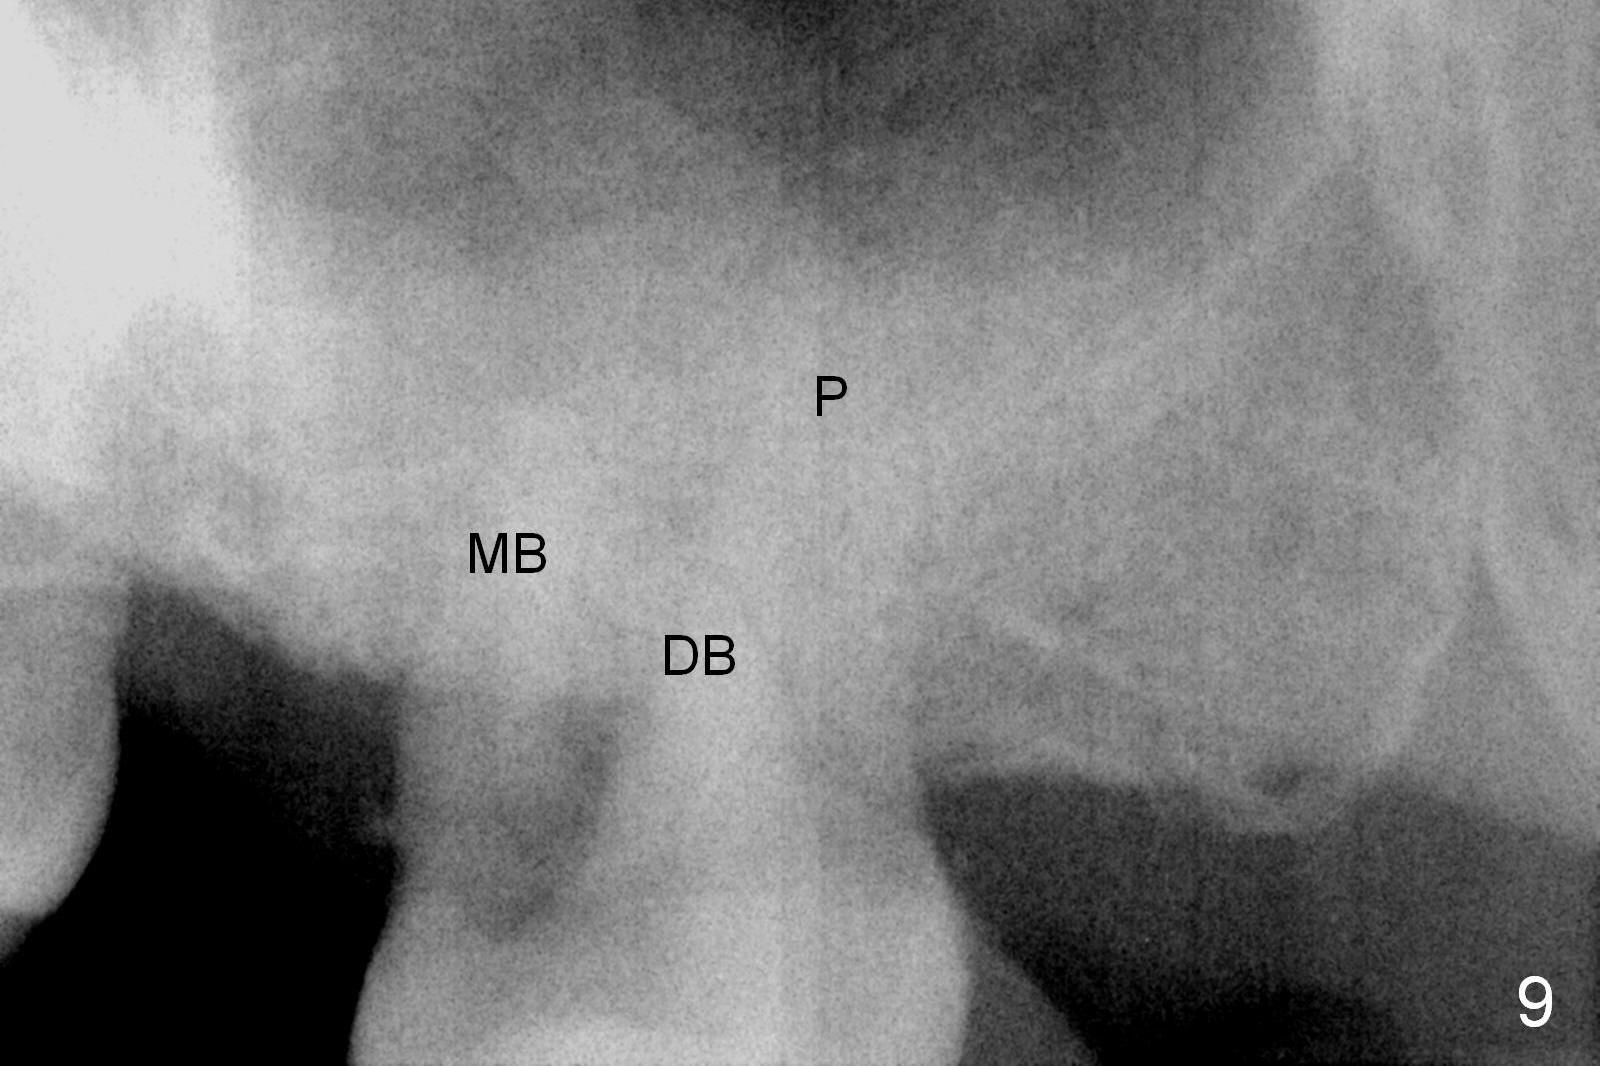

By comparing the root morphology of an extracted tooth (Fig.7,8: #15) with that of X-ray (Fig.9) repeatedly, we can develop an ability to visualize the septum prior to surgery.